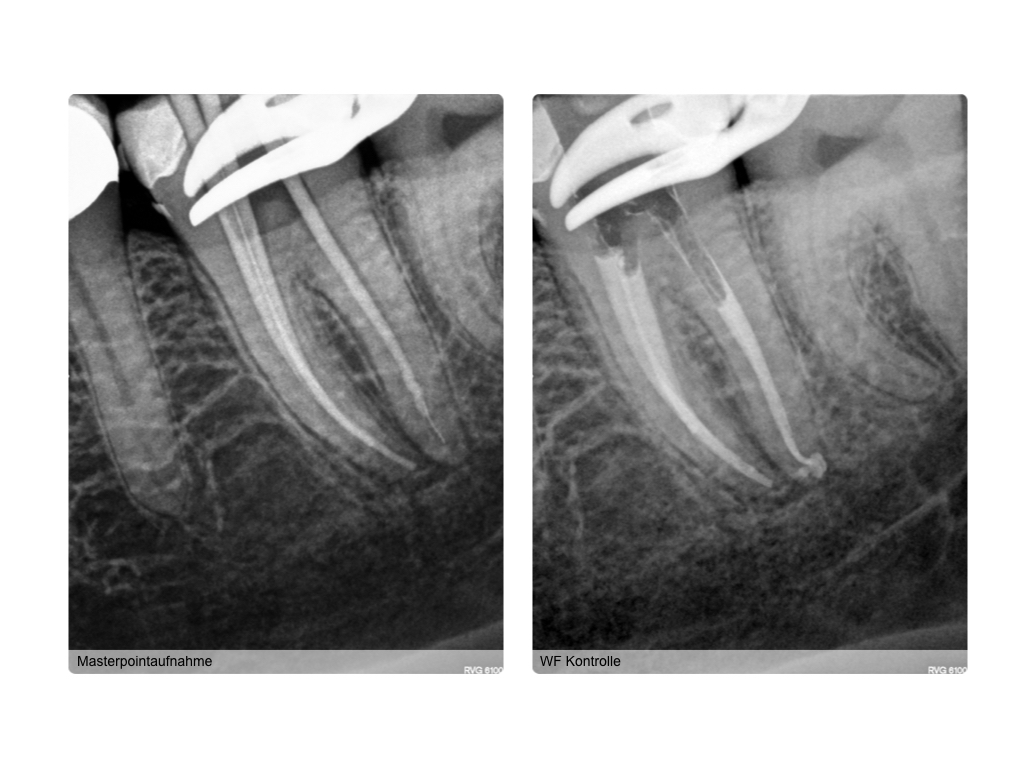

WS_Fallvorstellung15_12_12.007 Veröffentlicht 15. Dezember 2015 am 1024 × 768 in 2015 Fallvorstellung 2